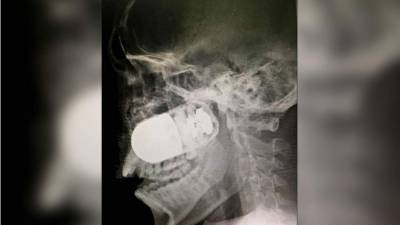

Cuando finaliza su contacto se ve como una mujer de alta estatura y fornida, vistiendo camisa verde aparece y trata de llamar su atención, al regresar a estudios, se ve cómo toma a la reportera del cuello y le deja ir un puñetazo en el rostro.